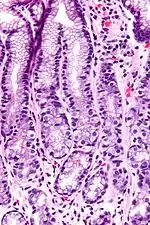

In anatomy, the G cell or gastrin cell is a type of cell in the stomach and duodenum that secretes gastrin. It works in conjunction with gastric chief cells and parietal cells. G cells are found deep within the pyloric glands of the stomach antrum, and occasionally in the pancreas[1] and duodenum. The vagus nerve innervates the G cells. Gastrin-releasing peptide is released by the post-ganglionic fibers of the vagus nerve onto G cells during parasympathetic stimulation. The peptide hormone bombesin also stimulates gastrin from G cells. Gastrin-releasing peptide, as well as the presence of amino acids in the stomach, stimulates the release of gastrin from the G cells. Gastrin stimulates enterochromaffin-like cells to secrete histamine.[2] Gastrin also targets parietal cells by increasing the amount of histamine and the direct stimulation by gastrin, causing the parietal cells to increase HCl secretion in the stomach. G-cells frequently express PD-L1 during homeostasis which protects them from Helicobacter pylori-induced immune destruction [3]

G cells have a distinctive microscopic appearance that allows one to separate them from other cells in the gastric antrum; their nuclei are centrally located in the cell. They are found in the middle portion of the gastric glands.